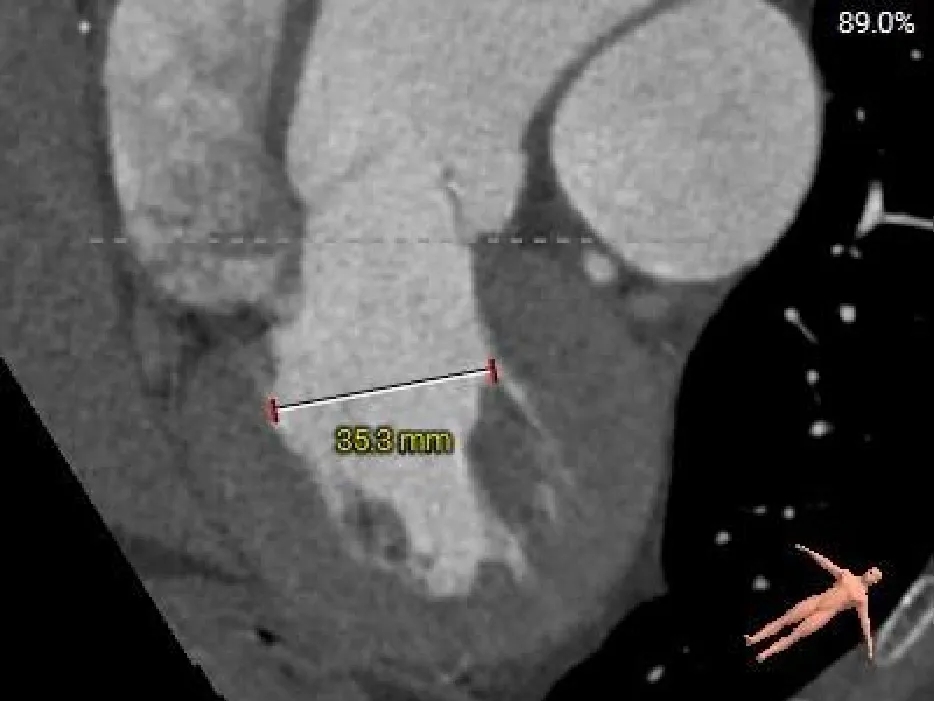

CASE Ⅲ

患者基本情况

基础信息:76岁,男性。

术前CT分析

主动脉根部测量

Annulus

25mm

LVOT

25.6mm

SOV

35.3*36.8*38.2mm

STJ

37mm

AAO

41.4mm

心脏角度

53°